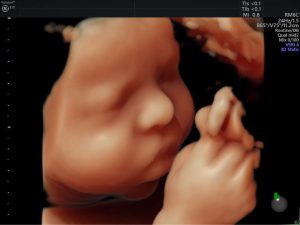

Siêu âm 2D, 3D, 4D là những phương pháp phổ biến nhất để kiểm tra ...

Siêu âm thai rất quan trọng trong suốt thai kỳ, giúp bác sĩ kiểm tra ...